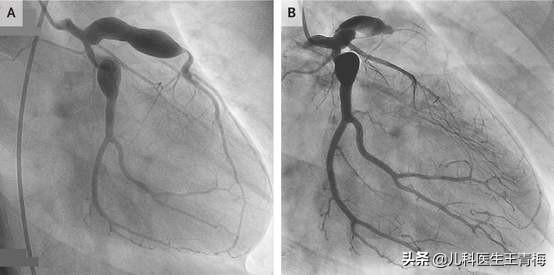

如不及时治疗,20%会出现冠状动脉损伤,从而引起冠脉扩张和冠状动脉瘤形成,这个瘤,只是形状像瘤,动脉根部膨出而已,并不是真正的肿瘤,但是它极度危险啊

读研的时候,有个川崎娃娃,啥啥都好的不得了,天天上着心电监护,一级护理,为啥呢,3岁的孩子,主动脉动脉瘤扩张,不知道啥时候会不会就破了,破了就连救的机会都没有,即便它不破吧,那些血液在里面兜个圈,形成血栓的概率也是大大增加,再随着心脏跳动去到别的脏器,分分钟各种梗啊,心梗,脑梗……

川崎病不可怕,怕的就是这个并发症,所以用药的目的减少冠状动脉瘤形成,用药那么久的目的,别形成血栓